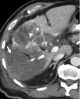

Liver tumor embolization